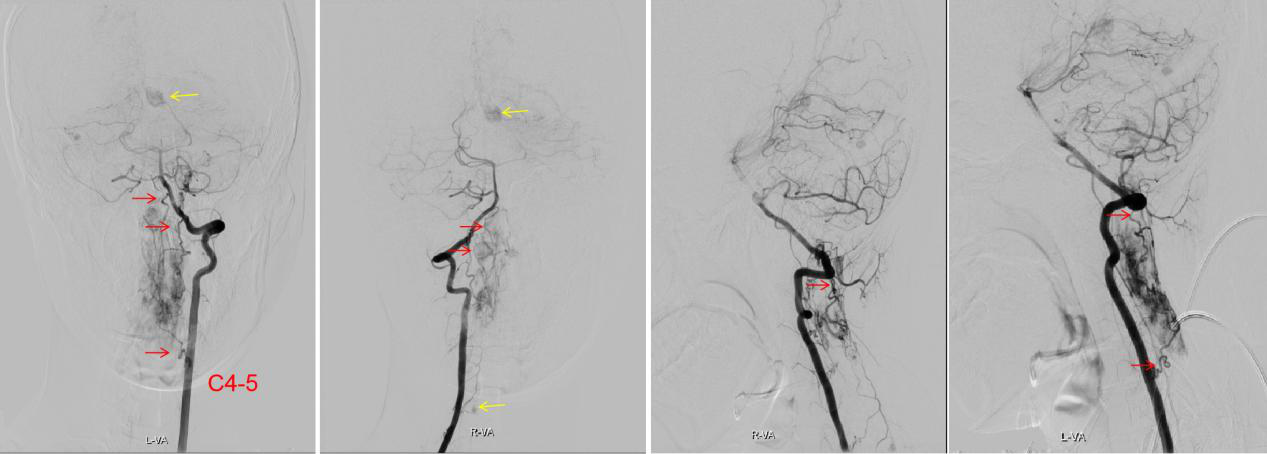

其实雯雯罹患的是一种常染色体显性遗传病——Von Hippel-Lindau综合征,这种病会造成中枢神经系统的多发血管母细胞瘤,同时还常合并肾脏或胰腺囊肿、嗜铬细胞瘤、肾癌以及外皮囊腺瘤等疾病,目前主要以手术治疗为主。对于有家族遗传史的病人,妊娠期需要做基因筛查,优生优育。考虑到雯雯目前病情紧急,已经出现四肢瘫痪和呼吸困难,住院后王贵怀教授团队紧急讨论制定了手术方案,先期处理延颈髓巨大血管母细胞瘤,术前行全脑和脊髓血管造影,明确肿瘤血供,彻底切除病灶。

图2 术前造影显示肿瘤血供丰富,左、右椎动脉均有供血